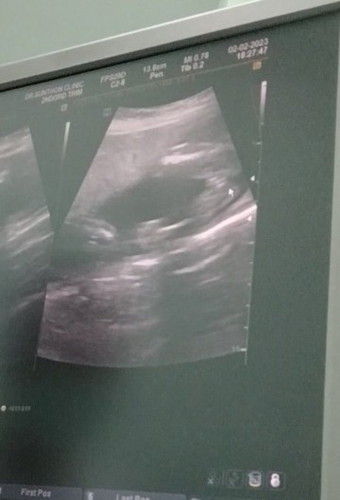

แม่ๆช่วยดูหน่อยค่ะน้องเป็นญรึชค่ะ

คุณหมอบอกน้องเป็นผญค่ะแม่ๆบ้านไหนซาวด์เห็นแบบนี้ไหมค่ะแร้วหมอบอกว่าญรึป่าวค่ะ😀

ผู้หญิงจ้า